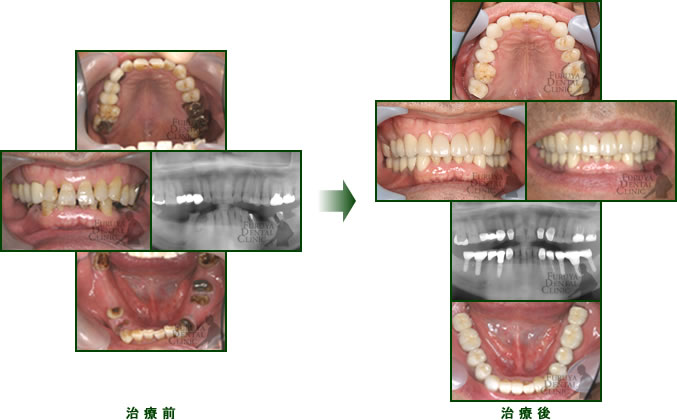

70代 女性

前歯、臼歯部に広範囲に欠損があり全体的咬合崩壊を起こしつつある症例。

歯周治療、補綴治療、インプラント治療で再構築